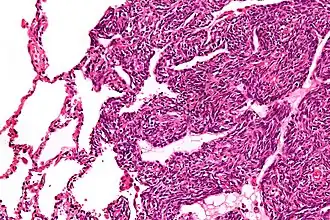

![]() Микрофотография из монофазной синовиальной саркомы | |

Опухоль состоит из разнообразных по форме клеток (то округлых, то напоминающих эпителий), среди которых расположены щели и полости различной формы и размеров, заполненные слизеподобными массами. Отмечается образование сосочковых структур, напоминающих синовиальные ворсинки (волокнистая саркома). Иногда опухоль имеет железистое строение и напоминает аденокарциному. В некоторых случаях (единичных) встречаются гигантские клетки.

- Монофазная